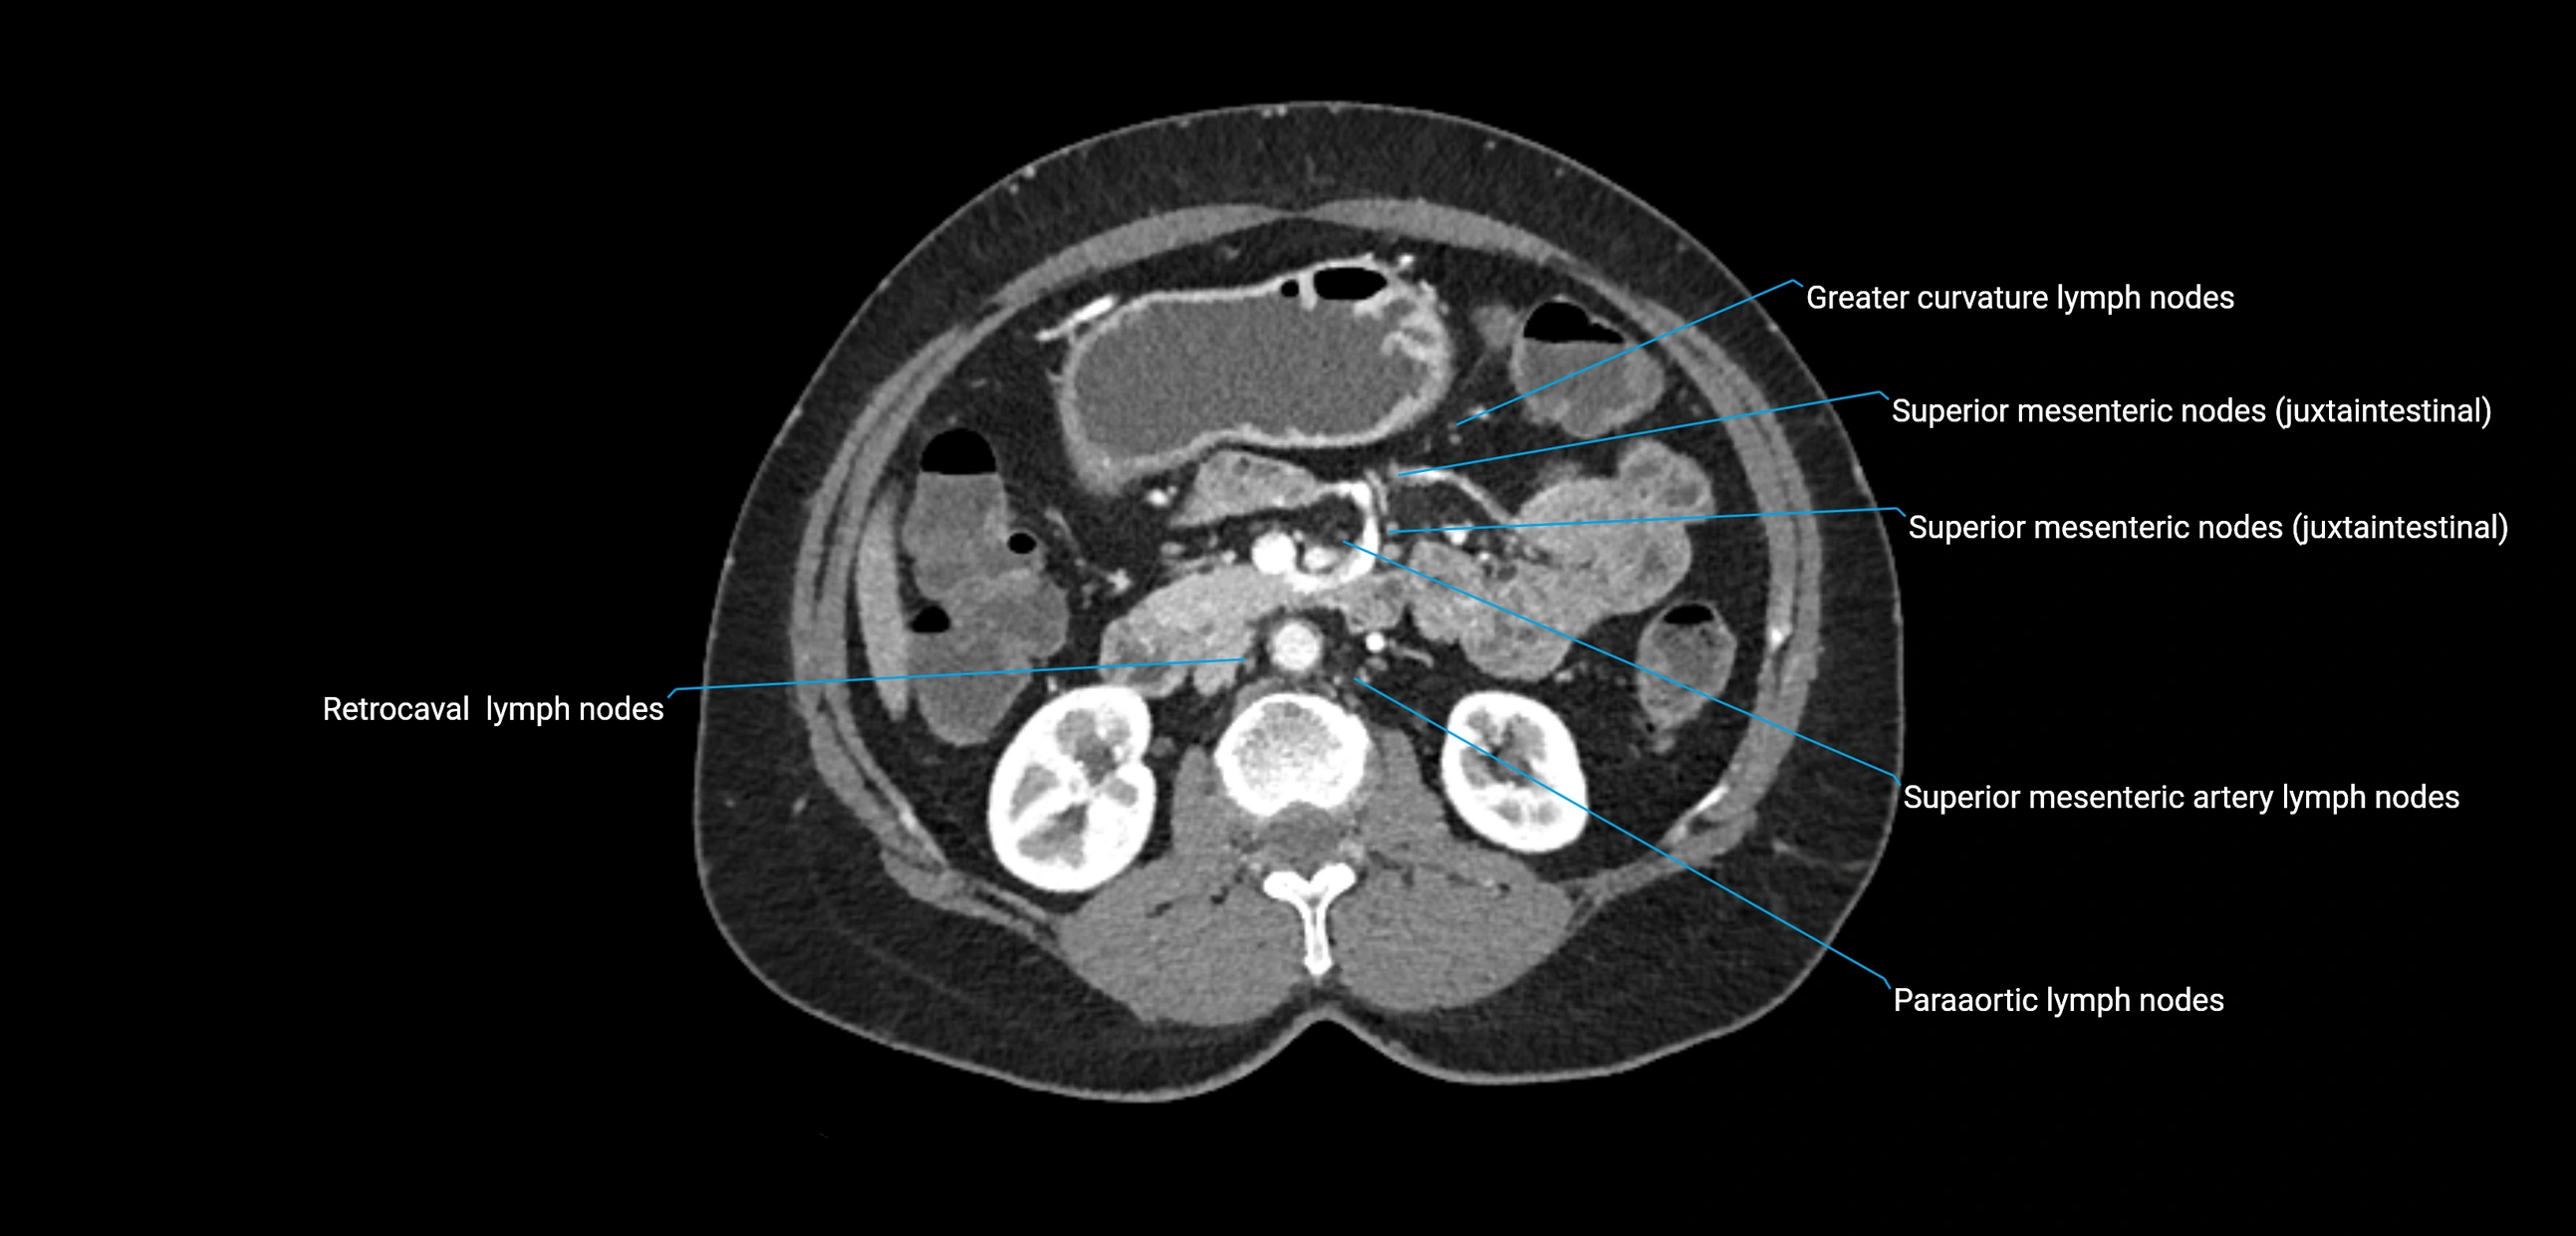

CT Appearance

CT Pre-Contrast:

• Nodes appear as soft-tissue density nodules adjacent to the aorta and IVC

• Calcification may be seen in chronic infections (e.g., tuberculosis)

CT Post-Contrast:

• Normal nodes enhance homogeneously

• Malignant nodes may show heterogeneous enhancement, central necrosis, or conglomerate formation

• Size >1 cm short axis is suspicious, though morphology and distribution are equally important

CT Venography (CTV):

• Demonstrates nodal encasement or compression of adjacent vessels (aorta, IVC, renal veins)

• Useful in staging testicular and ovarian malignancies

• Provides 3D reconstructions for retroperitoneal lymph node dissection planning